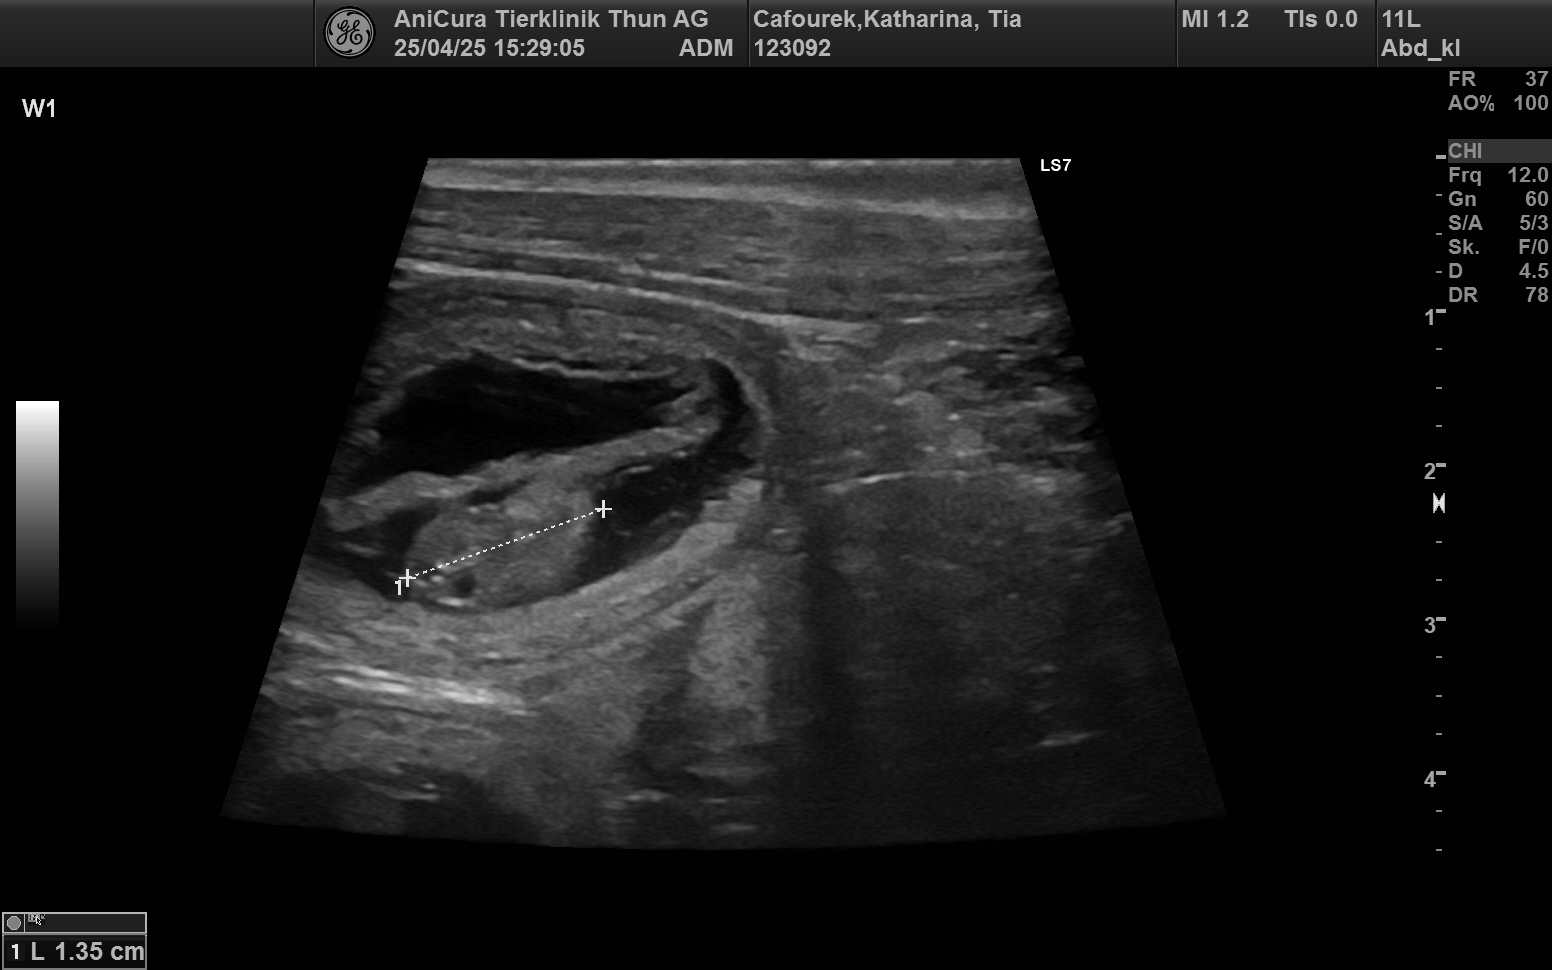

Shumbazino Hatia Feelena Tia und Hunterholm Dacapo Moyoni Mo werden Eltern

Wir freuen uns mit Katharina, dass ihr Traum von einer ersten Zucht bald in Erfüllung geht und wir wünschen Tia weiterhin eine komplikationslose Trächtigkeit.